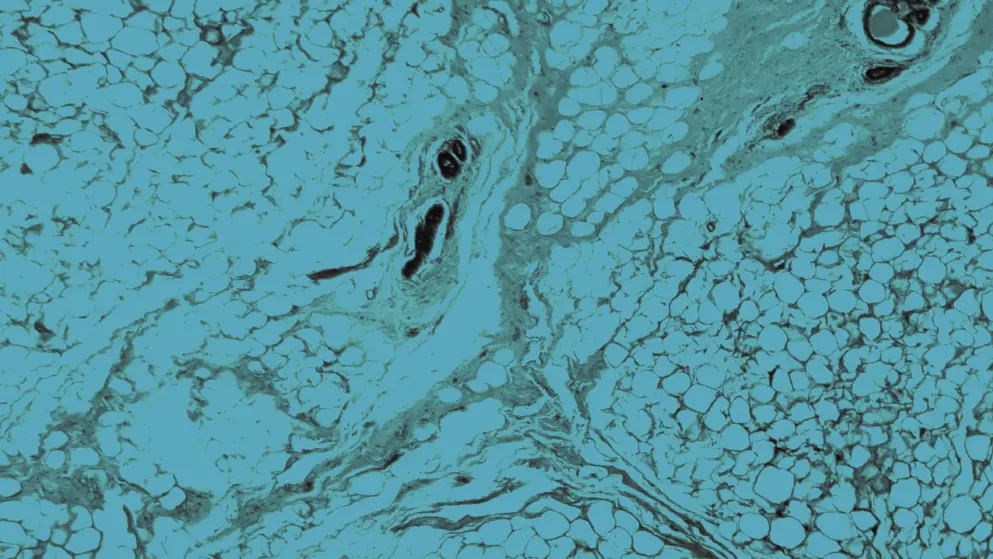

The most prevalent form, invasive ductal carcinoma (IDC), begins in the milk ducts and spreads into surrounding breast tissue. Lobular carcinoma, the second most common type, arises in the milk-producing lobules, and also spreads locally. By contrast, ductal carcinoma in situ (DCIS) is a non-invasive form confined to the ducts, without extension into surrounding tissue.